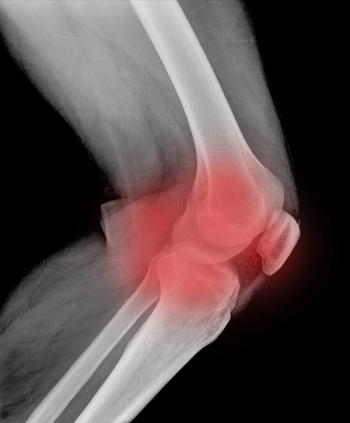

New findings from a national survey shed light on patient attitudes and experiences with arthritis and joint pain.

Findings from the University of Michigan National Poll on Healthy Aging highlight the need for clinicians to raise the topic of joint pain with their older patients.